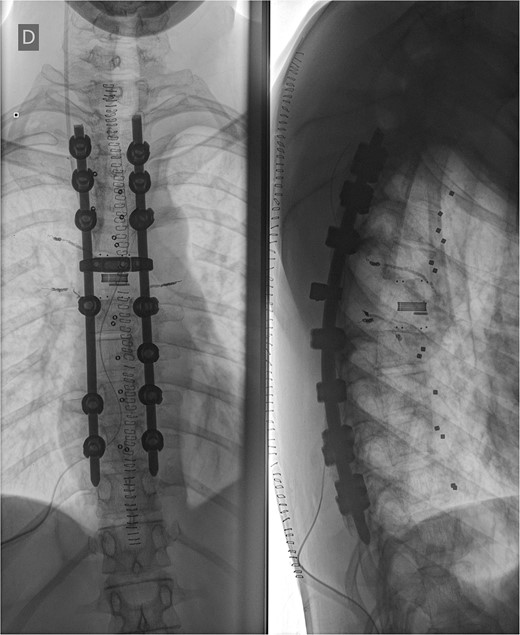

We decided to perform a revision total en bloc spondylectomy at Th6, along with resection of the Th8 pedicle and costovertebral joint, with a partial resection of the adjacent rib. Posterior spinal fixation from Th3 to Th10 was performed using radiolucent carbon screws, and the Th6 body was reconstructed using a radiolucent expandable cage (Figs 3 and 4). During the surgery, MEPs and SEPs were lost, with the patient waking up paraplegic (ASIA score B, VAS pain score 5). Immediate postoperative MRI showed no residual signs of thoracic spinal cord compression due to tumour or haemathoma (Fig. 5). The patient’s neurological status substantially improved the day after surgery, and thereafter, gradually improving over the next few days, allowing the patient to walk independently within 10 days (ASIA score D, VAS pain score 3). A multidisciplinary council decided against postoperative radiotherapy to avoid aggravating neurological symptoms by possibly causing additional damage to the myelopathic spinal cord. On the 11th postoperative day, the patient reported dyspnoea, and urgent CT angiography revealed peripheral pulmonary embolism, which was managed utilizing Deltaparine. Subsequent postoperative course was uneventful, leading to his discharge on the 15th postoperative day, ambulating independently using a walker. MRI follow-up was conducted 6 months postsurgery, followed by yearly checks. At the last follow-up, 2.5 years after the second surgery, there were no signs of tumour recurrence, and the patient exhibited no gait disturbance, back pain, or radiological signs of spinal instability (Fig. 6) (ASIA score E, VAS pain score 0).

Postoperative X-ray imaging immediately after surgery; anteroposterior view (left) and lateral view (right).